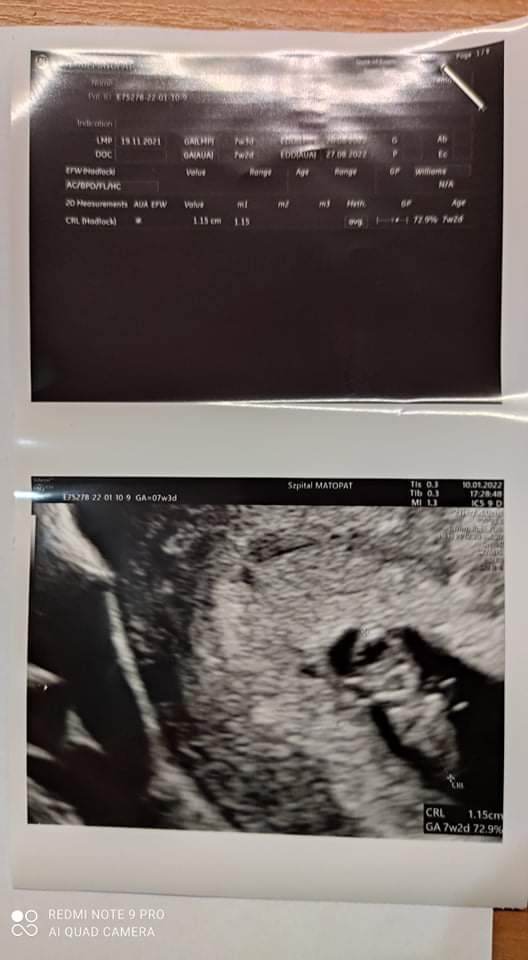

Chwalę się i ja 😉 naturalsik, w lipcu przestałam KP, w sierpniu dostałam okres, a w listopadzie ciąża, szok 😉